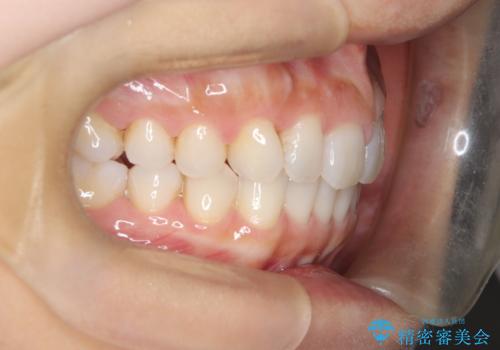

【インビザライン】前歯のねじれを治したい

- 前歯のガタガタを主訴に来院されました。

叢生の量は軽度でしたが臼歯の遠心移動を行い、インビザラインにて治療をしました。

叢生の改善に必要なスペースは遠心移動やIPRで作ることが可能です。今回は遠心移動をメインにスペースを作って叢生の改善を行いました。